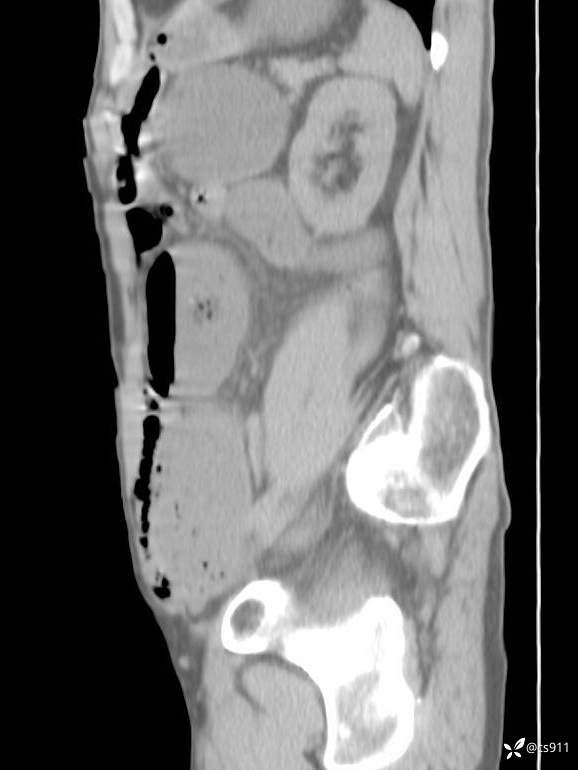

急腹症之急诊CT,原因?答案公布

男,77岁,腹痛、腹胀伴恶心呕吐1天。呕吐胃内容物,非喷射性呕吐,有咖啡色样胃内容物,诉有胃穿孔病史。查体:全腹平,下腹部压痛,全腹无反跳痛,叩诊呈浊音,移动性浊音阴性,肠鸣音减弱,1-2次/分。肛检:直肠未扪及明显肿物,可触及大量粪块。

T 36.6℃ P 80次/分 R 26次/分 BP 100/60mmHg

白细胞(WBC) H 14.55 10e9/L 4-10

红细胞(RBC) 4.58 10e12/L 4.3-5.8

中性粒细胞百分率(NEUT%) H 85.7 % 40-75

血淀粉酶(AMY) HH 1859 U/L 35-135

癌胚抗原(CEA) H 27.44 ng/ml 0-5

呕吐物 潜血试验 * 阳性 阴性

患者轮椅入室检查神志清楚, 能配合摆位和呼吸